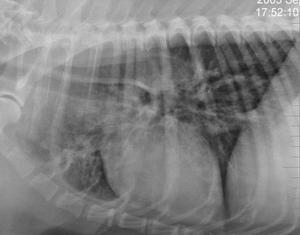

La miastenia a veces conlleva megaesófago

El megaesófago conduce a neumonía por aspiración

There may be an inciting febrile episode, but often no inciting cause is found. Animals present with weakness and exercise intolerance. There may be changes in bark, difficulty in swallowing and prehending food. Regurgitation and megaesophagus may be present.

Some cases present in a myasthenic crises where the animal has collapsed and is unable to rise. At this time, there may be muscle flaccidity. In uncomplicated myasthenia gravis (those without pulmonary pathology from aspiration pneumonia), the animal demonstrates progressive weakness on movement which improves with rest. Mild cases may be difficult to differentiate from animals with polymyositis.